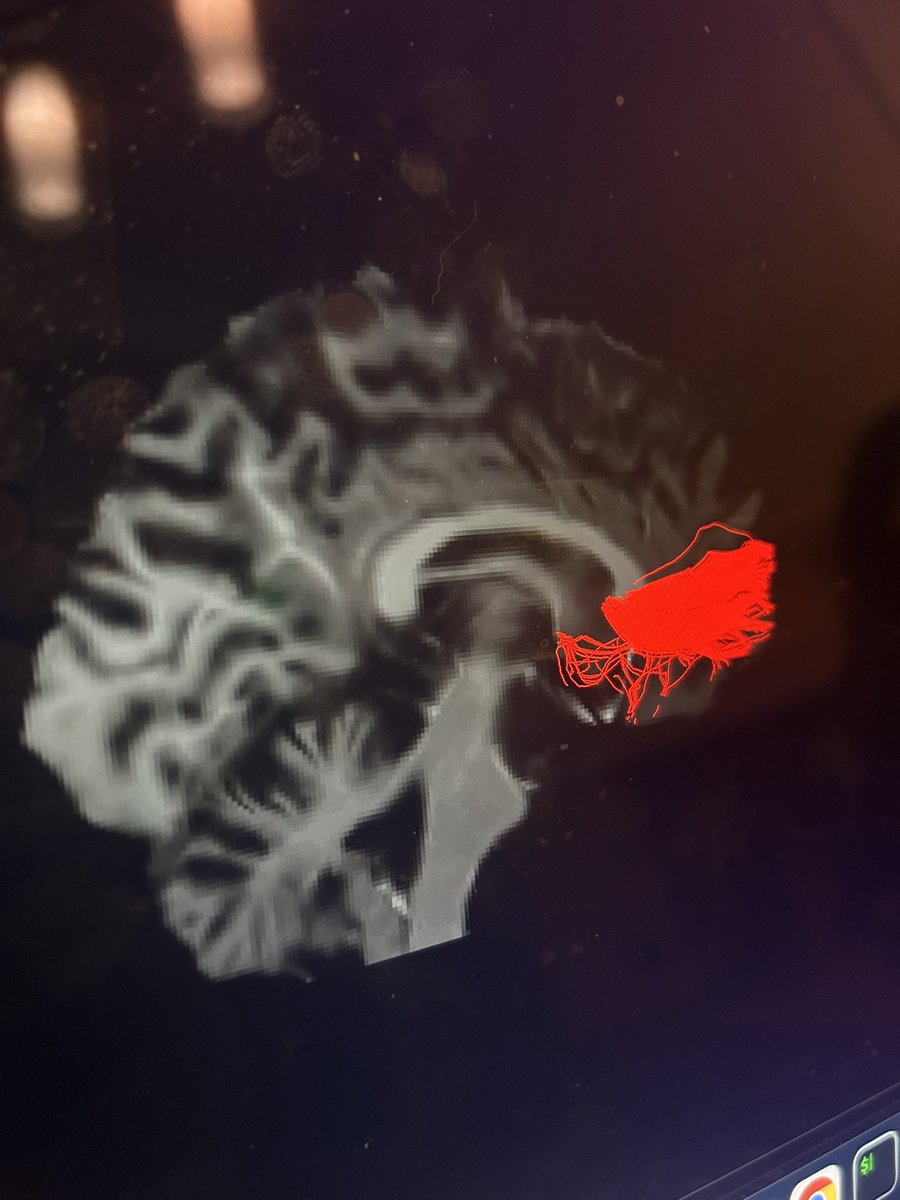

At the recent @vuiis Retreat, @AdamSaunders97 presented "Vasculature-informed spatial smoothing of white matter functional magnetic resonance imaging." This novel method smooths images along the vasculature to unlock insights into brain connectivity. @VanderbiltU